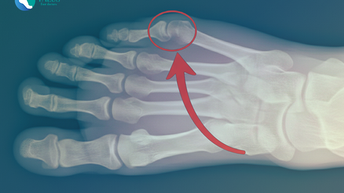

(IV) El juanete de sastre: la causa oculta del dolor en tu meñique que casi nadie conoce

El juanete de sastre o quintus varus provoca dolor en el borde externo del pie. Descubre sus causas, síntomas y los tratamientos más efectivos para aliviarlo, prevenir su avance y recuperar tu bienestar.

Dra. Laia López Capdevila - Talus Foot Doctors

10 dic 2025